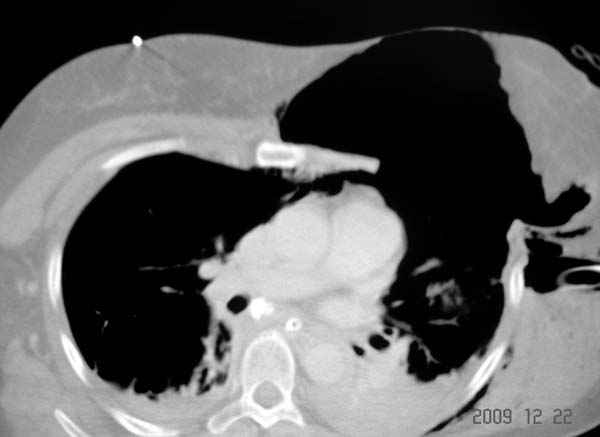

К нам поступила больная 56 лет после автоаварии в бессознательном состоянии, которая срочно заинтубирована в приемном отделении и сделаны необходимые исследования. Данные КТ и рентген показали перелом дистального бедра и Dissociation upper extremity - закрытый отрыв левой верхней конечности на уровне грудинно-ключичного сочленения и множественные переломы ребер.

Срочно в операционной наложен наружный фиксатор и травма хирургом поставлены трубки в плевральную полость.

На седьмые сутки нами совместно с торакальным хирургом сделана операция по фиксации грудинно-ключичного сочленения и переломов ребер.

Больная в данный момент с трахеостомой, стабильная, пришла в сознание. На сегодняшнем осмотре больная шевелит пальцами, что говорит об отсутствии повреждений нервов.